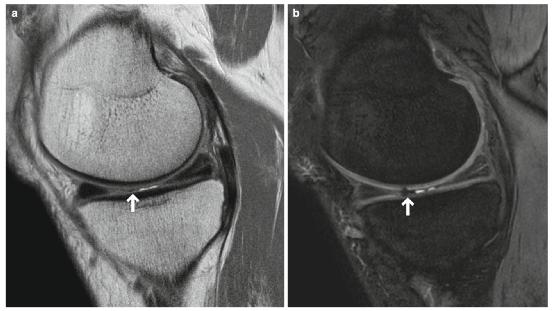

- 如果骨化变得足够大,可能会出现周围信号空洞(代表骨皮质)和来自脂肪骨髓的内部脂肪信号(图7.39)。

图7.39半月板骨化。一个40多岁的男性。(a ) PDWI,(b)冠状T2*WI,以及(c)常规X线照片。内侧半月板后角有骨化,包括脂肪骨髓(箭头)